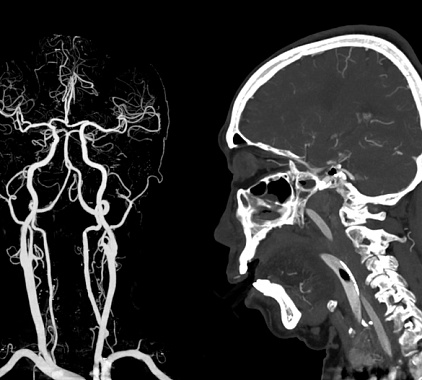

КТ сосудов головного мозга

КТ сосудов головного мозга (компьютерная ангиография) – это безболезненный и неинвазивный метод диагностики сонных и позвоночных артерий, а также вен. При проведении исследования используют контрастное вещество, которое вводится внутривенно. Во время процедуры получают трёхмерные снимки нужной области, позволяющие выявить патологические очаги на ранних стадиях. Компьютерная ангиография выполняется по направлению врача и по предварительной записи.

В процессе КТ сосудов головного мозга получают трёхмерные снимки, которые позволяют получить необходимую информацию о сосудистом русле. Готовые изображения передаются на компьютер и обрабатываются.

Компьютерная томография сосудов головного мозга позволяет увидеть выпячивания стенок сосудов, изменения движение крови, тромботическое поражение, атеросклеротические бляшки, эмболы, признаки ишемии и стеноза. В ходе исследования можно диагностировать опухоли, новообразования, пороки развития, васкулиты и ангиопатии, травмы и повреждения, инсульт.